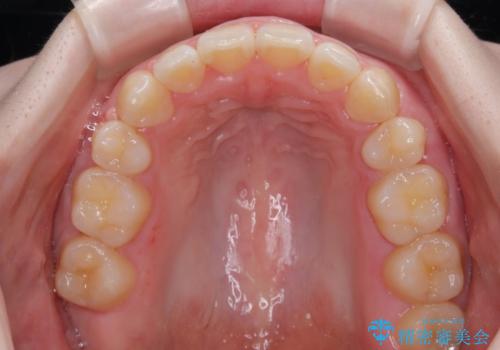

口元の突出感が改善されてことで、下唇に引っかかっていた上顎前歯も気にならなくなりました。